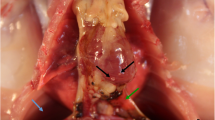

Body and organ weights are described in Supplementary Doc S2. The lungs of the MWCNT-7 treated rats were dark grayish in color at both weeks 3 and 52, while the r-nTiO2- and POT-treated rats showed normal external lung morphology. At week 52, the lungs of vehicle- and r-nTiO2 (0.25 and 0.5 mg)-treated rats showed normal lung histology (Fig. 1a, b); however, the lungs of the 0.50 mg POT- and 0.50 mg MWCNT-7-treated rats showed reactive bronchiolo-alveolar cell hyperplasia, thickening of the alveolar wall, and granulation tissue encasing the administered materials (Fig. 1c–f). Fibrotic changes with increased deposition of collagen in the alveolar wall, the areas around the bronchioles, in granulation tissue (Fig. 2), and in the sub-pleural tissues of the visceral and parietal pleura (Fig. 3) were observed in the 0.50 mg POT- and MWCNT-7-treated rats: Pulmonary collagen and the thickness of the visceral and parietal pleura are shown in Tables 1 and 2, respectively. Hyperplasia of the visceral mesothelium was found in two rats in the 0.50 mg POT group and in one rat in the 0.50 mg MWCNT-7-treated group (Fig. 4): Hyperplasia of mesothelial cells was confirmed by staining for mesothelin (Fig. 4).

Histological observation of lung tissue at week 52 of rats administered; a, b 0.50 mg r-nTiO2, c, d 0.50 mg POT fibers, and e, f 0.50 mg MWCNT-7. The lung histology of the untreated and vehicle control rats, and the rats administered 0.25 mg r-nTiO2-treated rats was similar to that of the rats administered 0.50 mg r-nTiO2 shown in a and b. The lung histology of rats administered 0.25 mg POT fibers was similar to, but less intense than, that of the rats administered 0.50 mg POT fibers shown in c and d. Black arrows indicate alveolar macrophages phagocytizing test materials. White arrows indicate granulation tissue. Striped arrows indicate thickening and hyperplasia of the alveolar epithelium. Inserts: polarized light microscope images

Three lung sections from each rat in the POT and MWCNT-7 groups were examined for granulation tissue. The average number of granulation tissue lesions found in the 0.50 mg POT-treated rats was 5.20 ± 2.28, which was significantly lower than the average number found in the MWCNT-7-treated rats, 56.40 ± 12.20, p < 0.001.

Numerous POT and MWCNT-7 fibers persisted in the lung at week 52. These fibers were mostly internalized in granulation tissue and the alveolar wall (Fig. 1c–f), but a considerable number of POT fibers were found free or partially engulfed by macrophages in the alveolar space (Fig. 1d). Macrophages were also found interacting with MWCNT-7 fibers (Fig. 1f).

Particles inhaled into the lung can translocate into the lymphatic system and hence into the pleural cavity (Harmsen et al. 1985; Miserocchi et al. 2008; NIOSH 2011). As in the lung, biopersistent particles retained in the pleural cavity can interact with pleural tissues and macrophages, and provoke repeated cycles of damage and repair and consequent fixation of DNA mutations into the genomes of mesothelial cells. In the present study, free POT and MWCNT-7 fibers were found in the pleural cavity lavage cell pellet, and collagen deposition at the visceral and parietal pleura, indicative of damage to the pleura, was also evident in these rats (see Fig. 3 and Supplementary Fig. S4). In addition, total protein concentration in the pleural cavity lavage fluid, an indicator of tissue integrity, was elevated in POT-treated rats (see Table 2). Finally, the PCNA indexes of both the visceral and parietal mesothelium were elevated in POT- and MWCNT-7-treated rats (see Table 2 and Supplementary Fig. S8), and importantly, two of the five rats in the 0.50 mg POT-treated group and one of the five rats in the 0.50 mg MWCNT-7-treated group had hyperplastic lesions in the visceral mesothelium (see Fig. 4).